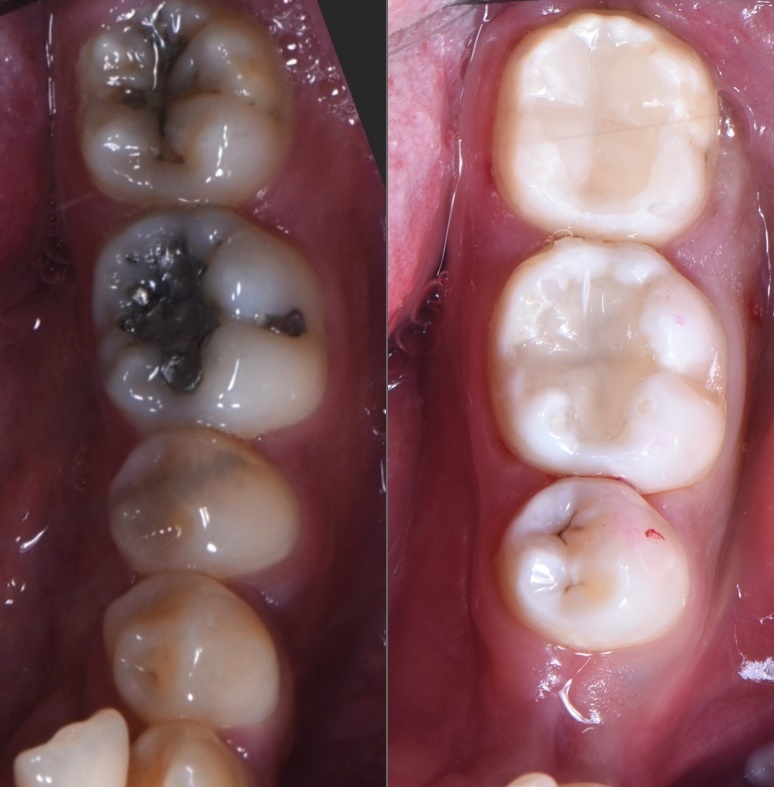

비포 앤 애프터 사진을 보시면 알 수 있습니다.

검게 썩어있던 깊은 충치는 깔끔하게 제거되었고, 특수 fiber를 이용한 레진빌드업으로 치아의 형태가 완벽하게 재건되었습니다.

고민 끝에 선택한 방법은 특수 fiber를 이용한 레진빌드업이었습니다.

이 환자분의 경우, 치아 높이가 너무 낮아 크라운을 씌울 기둥 자체가 부족했습니다.

그래서 기둥을 다시 세워야 했습니다.

특수 fiber를 이용한 레진빌드업은 이런 경우에 사용하는 고난이도 술식입니다.

단순히 충치 부위를 메우는 것이 아니라, 치아의 구조 자체를 재건하는 것이죠.